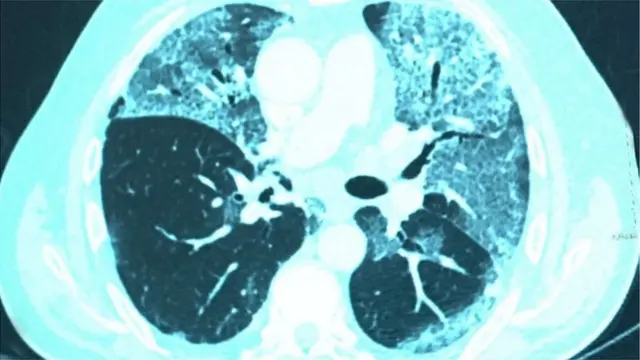

দেখা গেল, তাদের ফুসফুসের গুরুতর ক্ষতি হয়ে গেছে, অবসন্নতা ও বুক ধড়ফড়ানি দেখা দিচ্ছে, স্মৃতিশক্তি কমে গেছে, অনেকে এতটাই দুর্বল হয়ে পড়েছেন যে হাঁটাচলা পর্যন্ত করতে পারছেন না - স্বাভাবিক অবস্থায় ফেরত আসতে তাদের মাসের পর মাস সময় লাগছে, কাউকে কাউকে ফিজিওথেরাপি নিতে হচ্ছে।

"রোগীরা বলে, তারা মানসিক অবসাদে ভুগছেন, তাদের কিছু ভাল লাগছে না, কিছু করতে ইচ্ছা করছে না। কারও কারও হঠাৎ করে মনে হয়, শ্বাস বন্ধ হয়ে যাচ্ছে বা দম বন্ধ হয়ে যাচ্ছে। কারও কারও ফুসফুসে জটিলতা দেখা দেয়।"

অন্যদিকে ভাইরাস সংক্রমণে দেহের রক্তবাহী নালীগুলো ক্ষতিগ্রস্ত হলে হৃৎপিণ্ড, ফুসফুস এবং মস্তিষ্কের সমস্যা ঘটতে পারে।